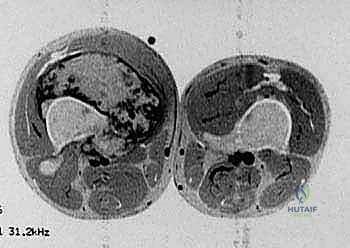

- التصوير بالرنين المغناطيسي (MRI): لتحديد الامتداد الدقيق للورم داخل العظم وفي الأنسجة الرخوة المحيطة (العضلات، الأوعية الدموية).

معرض الحالات الإشعاعية: توثيق النجاح الطبي مع د. محمد هطيف

الصور الإشعاعية قبل وبعد الجراحة هي الدليل القاطع على دقة ونجاح الإجراء الطبي. نستعرض هنا مجموعة من الصور التي توضح حجم الإنجاز الطبي في استبدال العظم المصاب بمفصل معدني متطور.